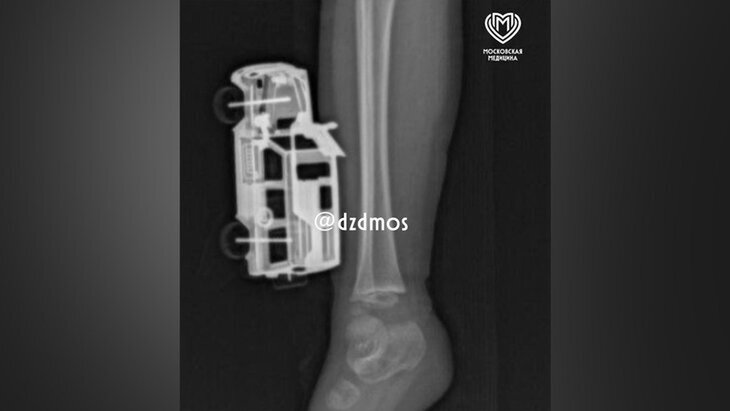

Фото: департамент здравоохранения Москвы

Специалисты Детской городской клинической больницы №9 имени Сперанского оказали помощь юному пациенту, у которого в голени застряла металлическая игрушечная машинка. Об этом заявили в пресс-службе Депздрава Москвы.

По информации ведомства, инородный предмет оказался в нижней конечности 4-летнего мальчика после того, как ребенок спрыгнул с кровати и неудачно приземлился на машинку.

В результате обследования врачи обнаружили, что игрушка вызвала повреждения мягких тканей правой голени. При этом некоторые части машинки вошли до подкожной жировой клетчатки.

В ходе операции медики успешно удалили игрушку и выполнили хирургическую обработку образовавшейся раны. Спустя сутки после процедуры мальчика выписали домой под амбулаторное наблюдение.